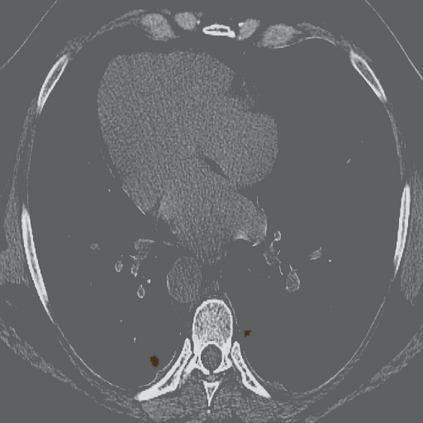

The novel coronavirus disease 2019 (COVID-19) has been spreading rapidly around the world and caused significant impact on the public health and economy. However, there is still lack of studies on effectively quantifying the lung infection caused by COVID-19. As a basic but challenging task of the diagnostic framework, segmentation plays a crucial role in accurate quantification of COVID-19 infection measured by computed tomography (CT) images. To this end, we proposed a novel deep learning algorithm for automated segmentation of multiple COVID-19 infection regions. Specifically, we use the Aggregated Residual Transformations to learn a robust and expressive feature representation and apply the soft attention mechanism to improve the capability of the model to distinguish a variety of symptoms of the COVID-19. With a public CT image dataset, we validate the efficacy of the proposed algorithm in comparison with other competing methods. Experimental results demonstrate the outstanding performance of our algorithm for automated segmentation of COVID-19 Chest CT images. Our study provides a promising deep leaning-based segmentation tool to lay a foundation to quantitative diagnosis of COVID-19 lung infection in CT images.

翻译:2019年新的冠状病毒疾病(COVID-19)在全世界迅速蔓延,对公共卫生和经济产生了重大影响;然而,对于有效量化COVID-19造成的肺感染,仍然缺乏研究;作为诊断框架的一项基本但具有挑战性的任务,分解在通过计算断层摄影(CT)图像测量的COVID-19感染的准确量化方面发挥着关键作用;为此,我们提出了对多个COVID-19感染区域进行自动分解的新型深层次学习算法。具体地说,我们利用综合残余变异学来学习一种稳健和直观的特征表征,并运用软关注机制来提高模型的能力,以区分COVID-19的症状。用公共CT图像数据集,我们验证了拟议的算法与其他相竞方法的功效。实验结果表明,我们自动分解COVID-19 Chest CT 图像的算法表现出色。我们的研究提供了一个充满希望的深度精细分解工具,为CT 图像中COVID-19肺感染的定量诊断奠定了基础。